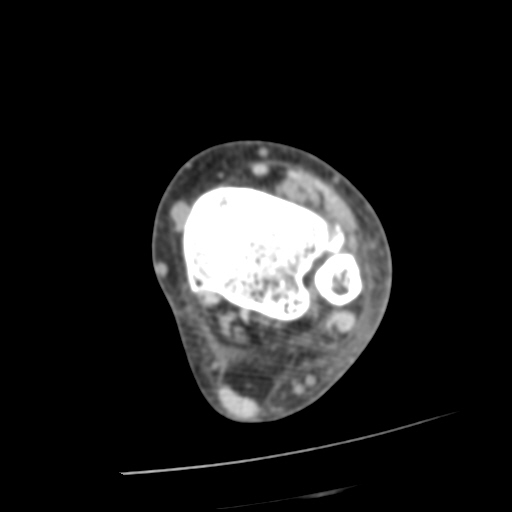

[¹ß¸ñ] distal tibiofibular ligament sprain with avulsion fracture of tibia

CT : avulsion fracture of distal tibia at distal tibiofibulat ligament insertion.